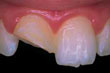

![]() | Diente frontal astillado |